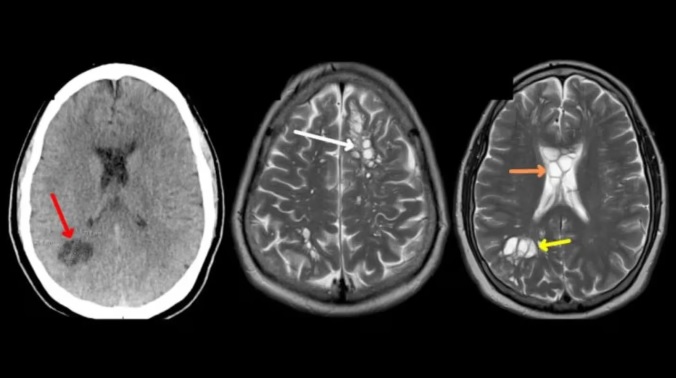

Ante la consulta del paciente, su médico de cabecera lo sometió a una tomografía en donde se logró visualizar una gran cantidad de quistes en la cabeza.